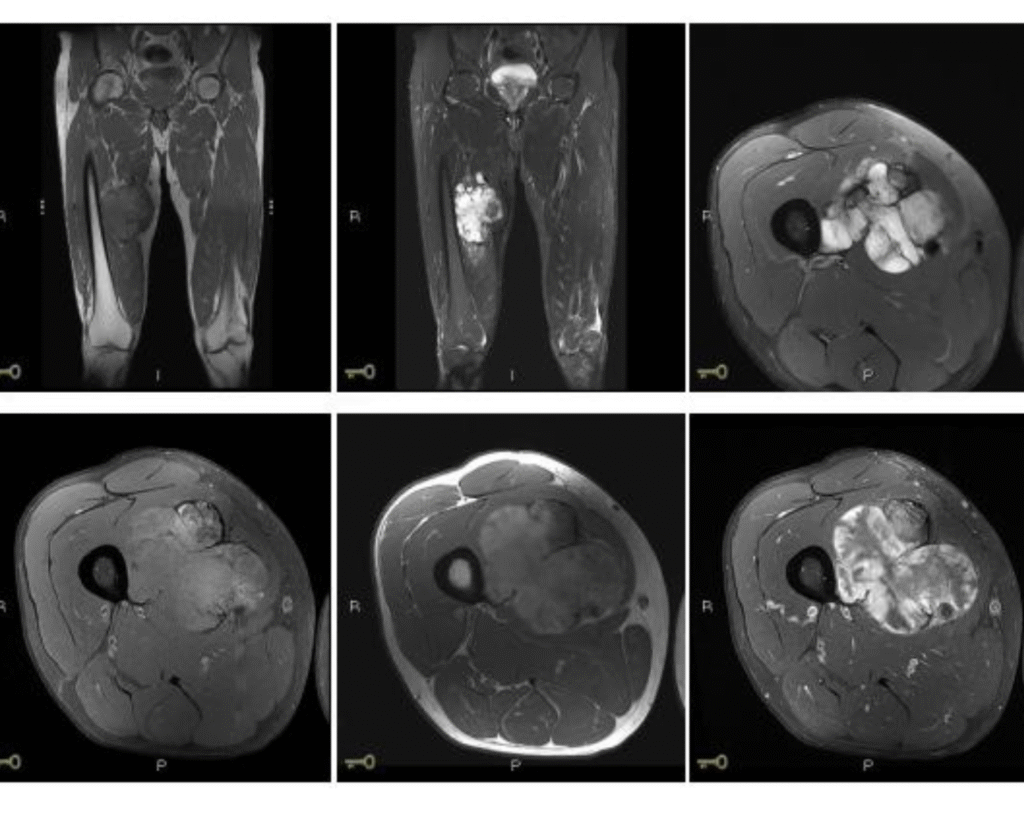

O que são sarcomas? Sarcomas são tumores malignos que se originam nos tecidos conjuntivos do corpo, incluindo ossos, músculos, tendões, fáscias, nervos, tecido adiposo e pele. São neoplasias raras, mas agressivas, que exigem um tratamento especializado, criterioso e multidisciplinar. Estão divididos em dois grandes grupos: sarcomas ósseos e sarcomas de partes moles. Entre os mais […]

A Importância da Cirurgia Oncológica Ortopédica no Tratamento de Tumores Musculoesqueléticos A cirurgia oncológica ortopédica desempenha um papel fundamental no tratamento de tumores musculoesqueléticos, abrangendo tanto tumores ósseos quanto tumores de partes moles, como músculos, tendões, nervos, tecido adiposo e pele. A indicação para o procedimento é baseada em uma avaliação criteriosa do tipo de […]